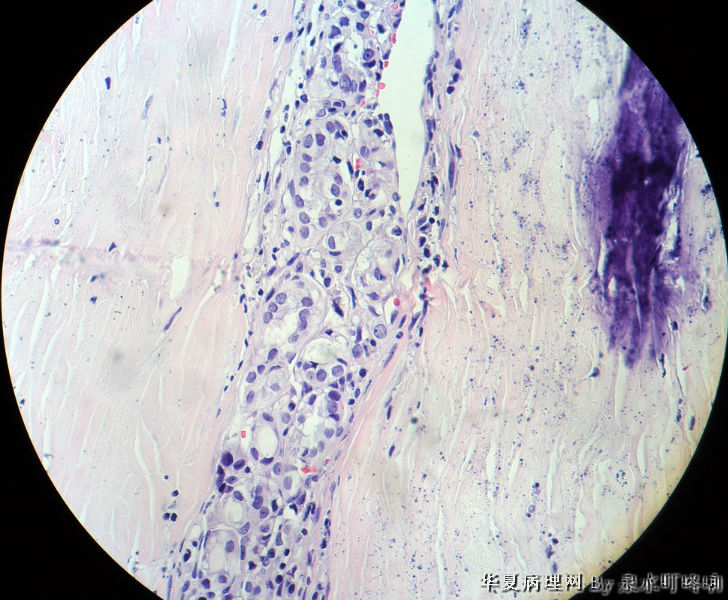

120212,女,55岁,左颈部肿物七年余。

大体:灰白肿物一个,大小约2.1×1.5×1.3厘米。表面光滑,包膜完整,切面灰白,部分包膜有钙化。

与手术医生沟通,肿物位于左颈部靠近甲状腺部位,比较浅(门诊手术),手术医生认为是淋巴结部位。

甲状腺滤泡状癌,有包膜浸润及血管内瘤栓

甲状腺滤泡性肿瘤,可见包膜及血管侵犯,考虑滤泡癌。

会诊结果:(颈左)考虑为甲状腺滤泡亚型乳头状癌,请结合临床进一步确认。